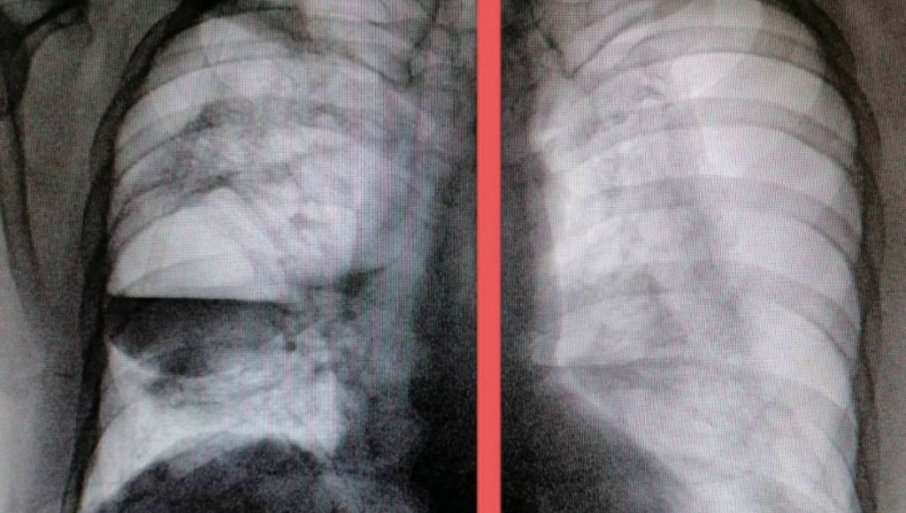

Фото:Твитер

- Он је сад стабилан, али још увек није добро. Када здравствено стање пацијента буде довољно добро, вероватно ће бити урађена хируршка интервенција, која је индикована у оваквим ситуацијама - каже др Плавшић.

Пуцање плућне марамице се дешава релативно често и код здравих особа. Проблем је у томе што се ова компликација десила пацијенту који већ болује од ковид 19 пнеумоније.

- Зато ми је ова компликована радиолошка слика била јако необична и зато сам саветовала да се пацијент хитно упути у референтну терцијалну установу, која се бави овом проблематиком - каже нам др Плавшић.